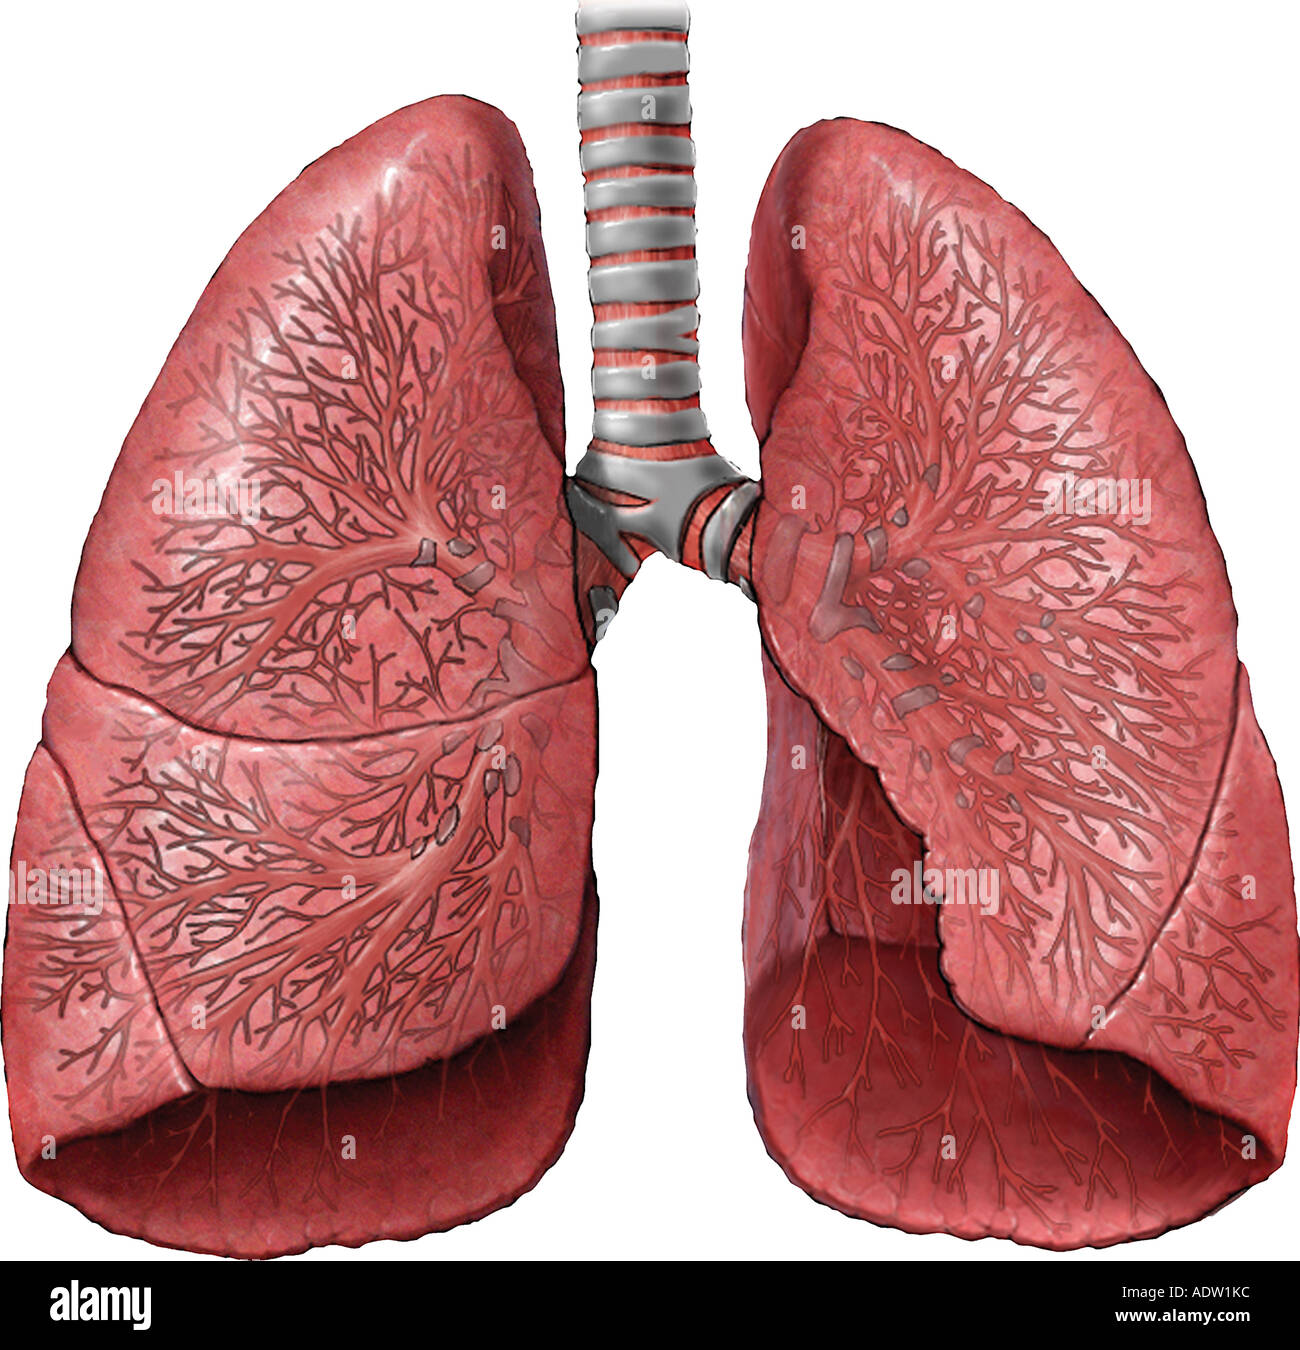

lung lungs lobes fissures middle inferior divided thorax

lungs lobes fissures right left oblique both teachmeanatomy lung structure thorax fig similar position info

lungs heart posterior vessels trachea bronchi pulmonary illustration

lung lingula anatomy lungs mediastinal posterior medial vertebral surfaces hilum anatomyqa

lungs lobes neet fissures exams mcqs mediastinum gpat

lungs thorax posterior anterior pulmonary mhmedical 1901

lung lungs pulmonary lecturio vessels

anatomy lungs respiratory system physiology human nurseslabs lung nursing body right breathing organs left main airways medical its board systems

lungs trachea bronchi poumons mediastinal

lung thorax hilum lungs medial apex britannica anatomy root function mediastinal

lungs lung diseases lobes

anatomy surface respiratory physiology examination lung relevant lungs lobe ribs middle lower epomedicine fissure upper posteriorly oblique costal sternum floating

lungs anatomy figure physiology gross labeled major

respiratory anatomy system lung gross apex presentation superior left lungs ppt powerpoint inferior base hilum right fissures pleura slideserve

Lungs lobes fissures right left oblique both teachmeanatomy lung structure thorax fig similar position info. Pin on bronchial anatomy. Topography of the lungs (posterior view) the apex of the lung extends